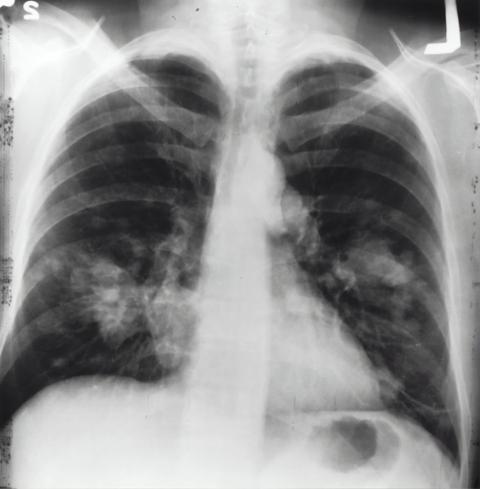

Preoperative imaging findings